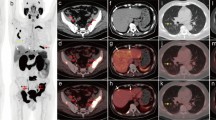

Fig. 2

PET images with scatter correction (b, e) compared to attenuation-corrected PET images without scatter correction (c, f) in the only patient (patient 8) who showed visually less bright lesions around the urinary bladder. All other patients demonstrated brighter PSMA-positive tissues/lesions on PET images with scatter correction. a Fusion of PET and CT images, d PET image from the PET/CT system, b fusion of PET and MRI (T1 native) images corrected for scatter and attenuation, e MIP image corrected for scatter and attenuation, c fusion of attenuation-corrected PET image without scatter correction and MRI (T1 native) image, f attenuation-corrected MIP image without scatter correction. (JPEG 40 kb)

Fig. 3

Images in patient 8 with a significant halo around the urinary bladder which is clearly visible using extreme windowing in PET images with attenuation and scatter correction (d). Within the halo, SUVs are underestimated as demonstrated by VOIs in muscle inside and outside the halo (d). Extreme windowing can help detect suspicious lesions such as the suspicious lymph node (white arrows). This suspicious lymph node would not have been detected using the automatic windowing. a MR image (T1 with contrast medium and fat saturation) and b PET/MRI fusion image with attenuation and scatter correction as automatically produced by the PET/MRI system; c MR image (T1 with contrast medium and fat saturation) and d PET/MRI fusion image with attenuation and scatter correction with extreme windowing of the PET image. (JPEG 53 kb)